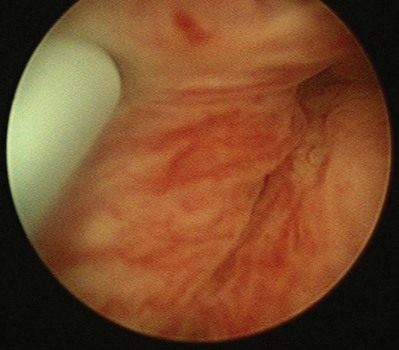

The patient is placed in the lithotomy position and prepared and draped in the usual sterile fashion. Topical 2% urethral lidocaine jelly is instilled into the meatus. Perimeatal blebs are raised with 1% or 2% aqueous lidocaine at the 3- and 9-o’clock or 4- and 8-o’clock positions 3 to 4 mm lateral to the urethral meatus with a 25-gauge needle. A 20-Fr urethroscope with a 30-degree telescope is inserted into the urethra. The periurethral needle is introduced and advanced parallel to the endoscope sheath until its position can be seen cystoscopically just below the bladder neck within the mucosa. The surgeon can hold the cystoscope in one hand and advance the needle with the other. Care must be taken to prevent the needle from getting too close to or entering the urethral lumen because rupture of the mucosa and extravasation will occur. Rocking the needle will confirm the position of the tip. If penetration of the mucosa occurs, the needle should be removed and repositioned. The substance is injected either unilaterally or bilaterally to create the appearance of “prostatic” lobes (Fig. 74–5). Transvaginal injection with the needle placed through the biopsy port of an ultrasound probe has also been described (Appell, 1996).

Figure 74–5 Appearance of urethra after injection of collagen with a transurethral needle that is seen on the left. Both sides of the urethra have been injected, giving the appearance of an occlusive prostate.